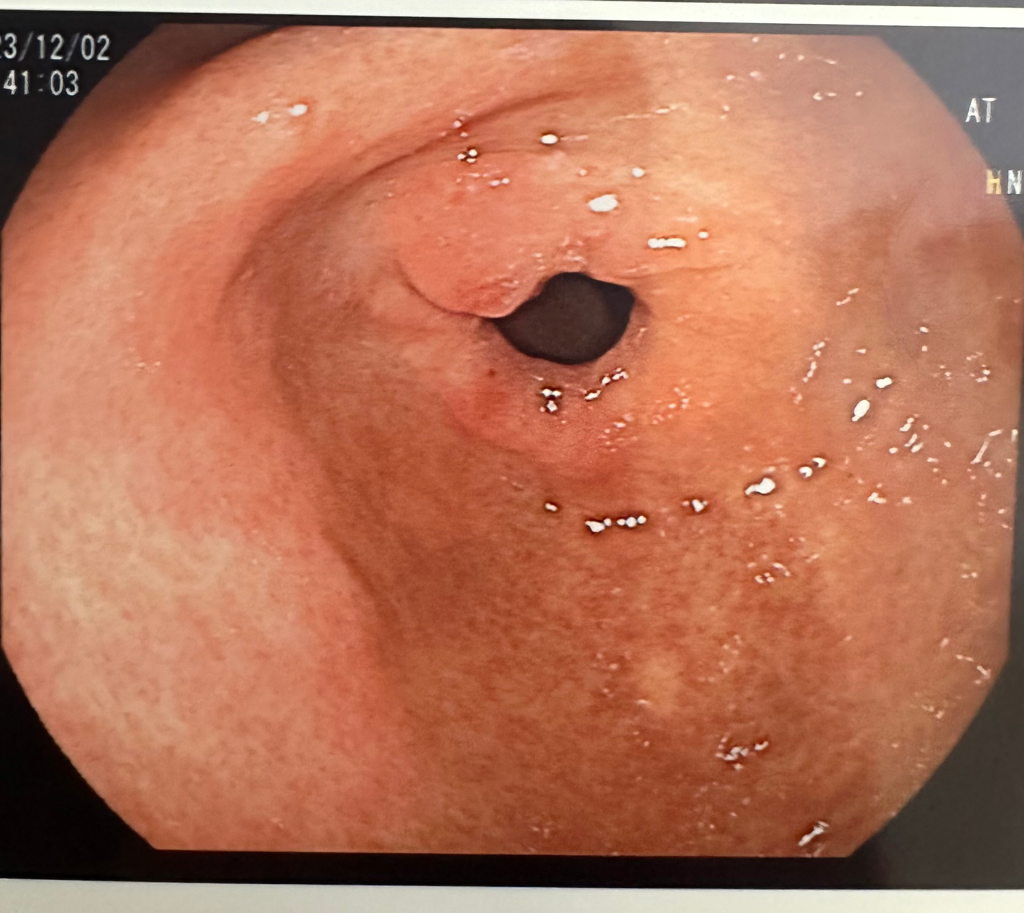

어제 위 내시경을 받았는데 불룩한게 있어서 조직검사를 했다고 하시더라구요. 살짝 까진 거 제외하곤 깨끗하다고 하셨는데 저 불룩한것도 단순 염증인걸까요?ㅠㅠ

• 1번 째 사진

관찰 소견이 기술된 판독지가 없어서 답변 드리기 어렵습니다. 정지 사진 1장만으로는 잘못된 정보를 드릴수 있기 때문입니다. 걱정되는 마음은 이해되지만 조직검사 결과를 확인하시기 바랍니다.